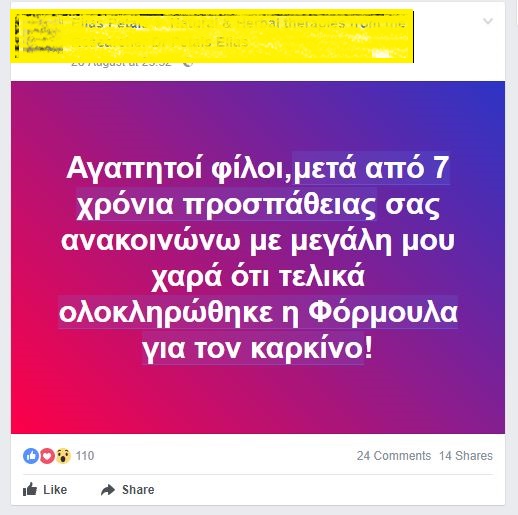

“Αγαπητοί φίλοι, μετά από 7 χρόνια προσπάθειας, ολοκληρώθηκε η φόρμουλα για τον καρκίνο” με αυτή την έκφραση ανακοίνωσε γιατρός στην Κύπρο σε ανάρτηση του στο Facebook το “επίτευγμα”. Όπως ήταν αναμενόμενο έντονες αντιδράσεις καθώς η φόρμουλα του είναι αμφίβολης ποιότητας.

Σύμφωνα με τον ίδιο, η “θεραπεία” του καταστρέφει τα καρκινικά κύτταρα και κοστίζει 688 ευρώ. Όπως παρουσιάζεται στις αναρτήσεις του είναι Καρδιοχειρούργος και Ερευνητής.

Παλαιότερα ανέφερε ότι η “φόρμουλα” του έχει τις εξής ιδιότητες:

Advertisement1. Ενισχύει το ανοσοποιητικό σύστημα2. Σκοτώνει μόνο καρκινικά κύτταρα

3. Καταστρέφει το DNA των καρκινικών κυττάρων4. Η φόρμουλα περιέχει επίσης, μια φιάλη από εκχύλισμα βοτάνου, το οποίο είναι 55ml5. Περιέχει καψούλες λυκοπεανίου για 8 μήνες6. Εκχύλισμα βοτάνου που μπορεί να χρησιμοποιηθεί ως τσάι7. Μια ένεση και ανάλογη σωστή διατροφή.

Ο γιατρός είχε στο παρελθόν προβλήματα με την Επιτροπή Δεοντολογίας και το Πειθαρχικό Συμβούλιο Ιατρικού Σώματος. Μετά την αθώωση του, δήλωσε σε άλλη ανάρτηση πως “ο δικηγόρος μου είπε να κρατώ χαμηλούς τόνους μετά και την αθώωση μου και να μην αναρτήσω άλλα περιστατικά για τους γνωστούς λόγους”.

Οι αρχές μετά την ανάρτηση του εν λόγω γιατρού ξεκίνησαν έρευνα για τους ισχυρισμούς του και σύμφωνα με δημοσίευμα του Πολίτη, ο Παγκύπριος Ιατρικός Σύλλογος εξετάζει και το ενδεχόμενο να υπάρξουν και πειθαρχικά αδικήματα εναντίον του.